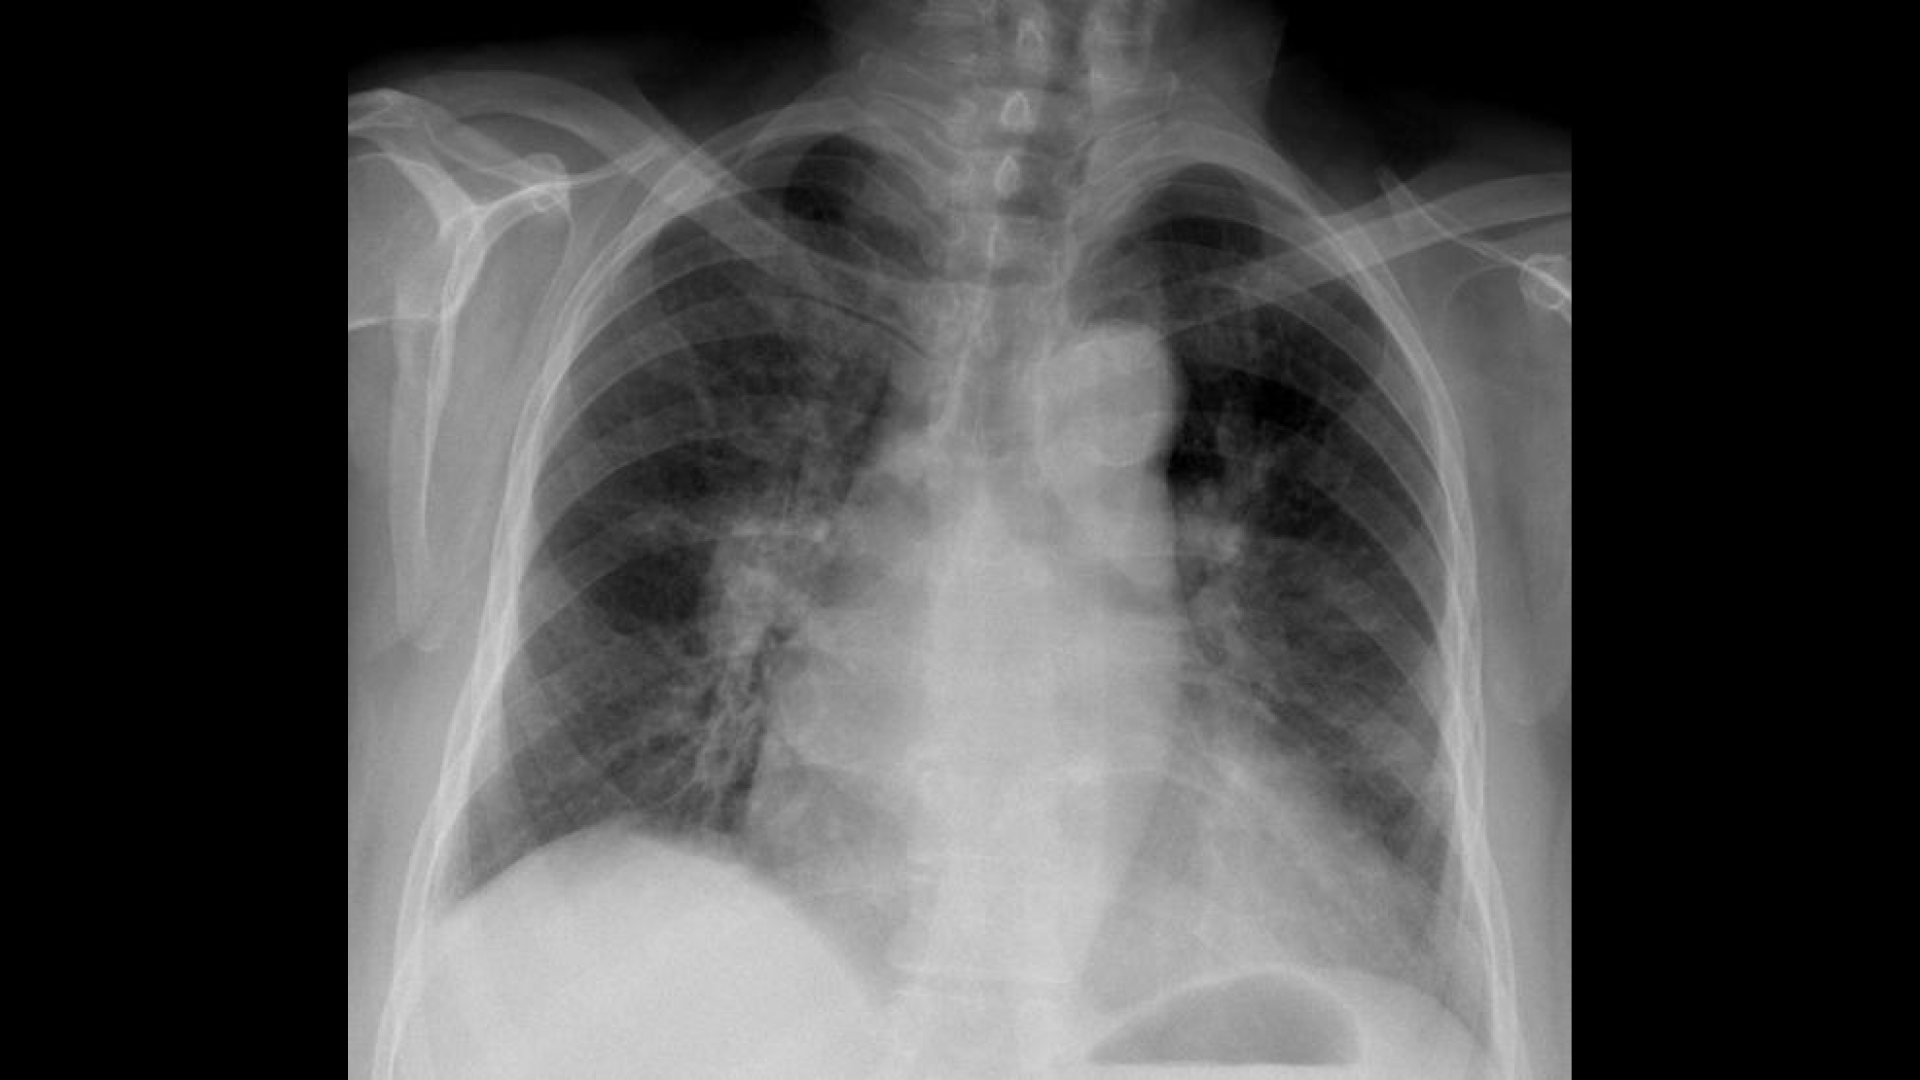

You need to find the diagnosis. First, analyze the picture and the different elements that are given to you. Take a paper and note down all the clues and arguments that will lead you to the right diagnosis. When you are finished, start a debate with the colleague of your choice in the next section!